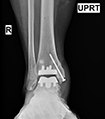

Ankle Joint replacement has dramatically improved the treatment of ankle arthritis over the past decade leading to decreased pain and an improvement in function.

The development of patient-specific technology has further enhanced the accuracy of implant alignment and decreased the surgical time.